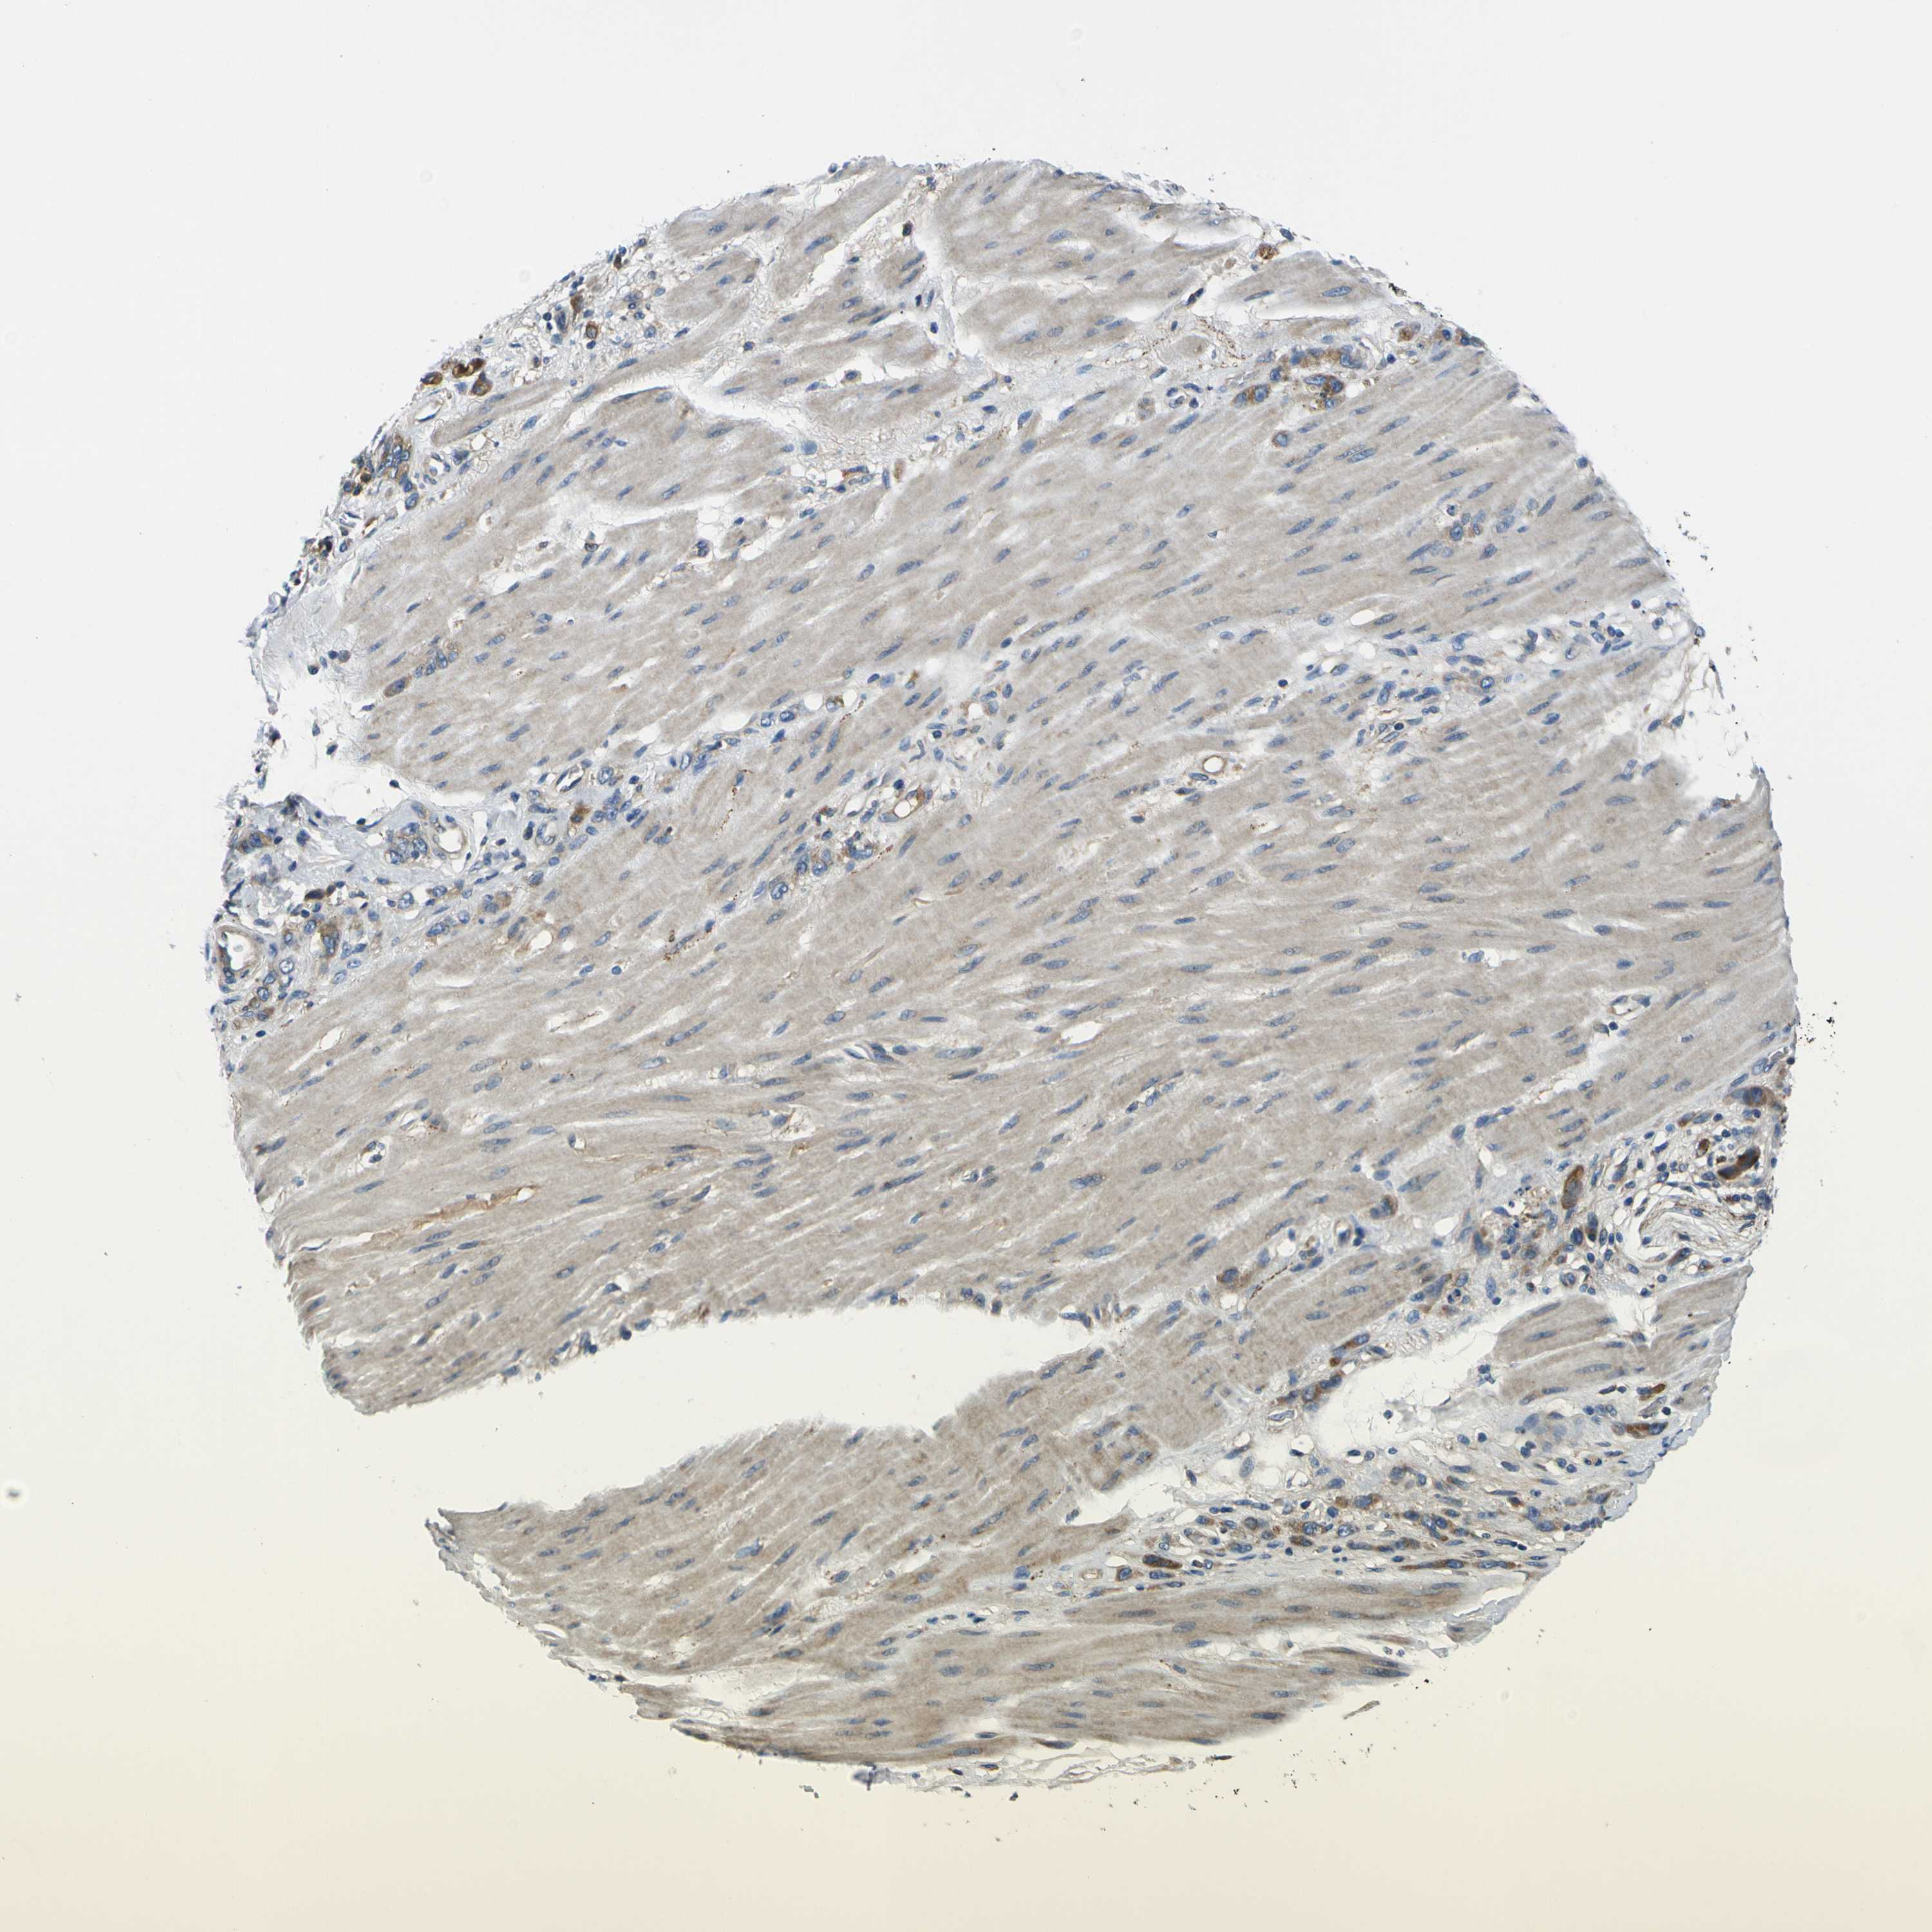

STOMACH CANCER - Protein expressioni

A mouse-over function shows sample information and annotation data. Click on an image to view it in a full screen mode. Samples can be filtered based on level of antibody staining by selecting one or several of the following categories: high, medium, low and not detected. The assay and annotation is described here.

Antibody stainingi

Antibody staining in the annotated cell types in the current human tissue is reported as not detected, low, medium, or high, based on conventional immunohistochemistry profiling in selected tissues. This score is based on the combination of the staining intensity and fraction of stained cells.

Each image is clickable and will lead to virtual microscopy that enables deeper exploration of all samples and also displays staining intensity scores, fraction scores and subcellular localization as well as patient and tissue information for each sample.

Antibody HPA056141

Antibody CAB010225

Staining

High

Medium

Low

Not detected

Intensity

Strong

Moderate

Weak

Negative

Quantity

>75%

75%-25%

<25%

None

Location

Nuclear

Cytoplasmic/membranous

Cytoplasmic/membranous,nuclear

Adenocarcinoma, NOS

Adenocarcinoma, High grade